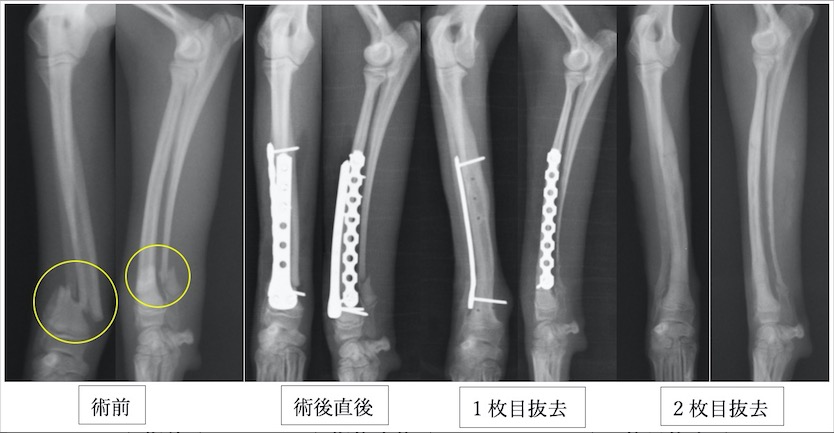

チワワの橈尺骨骨折です。1.5mmスクリューを使用しています。

2症例ともに橈尺骨遠位端骨折です。骨折端が短すぎて直線のプレートが入らない(スクリューを3本入れる必要があります)ため、正面にT字型のプレートを使用しています。